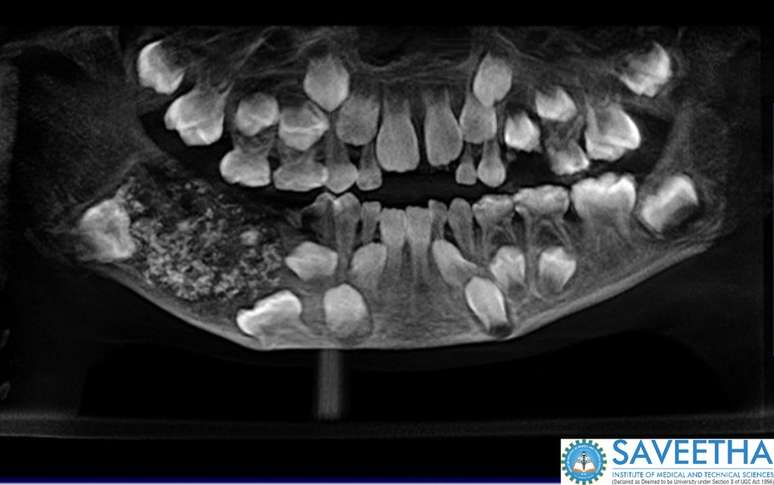

Exame de imagem mostra má-formação na dentição de garoto com odontoma composto

Foto: Saveetha Dental College and Hospital / Divulgação

Um menino indiano de 7 anos foi levado ao hospital pelos pais com queixa de inchaço no maxilar. Na época, em 2019, ele foi avaliado e, com ajuda de exames de imagem, foi comprovado que ele tinha uma grande lesão com múltiplas estruturas rígidas em um único local na mandíbula.

Após a intervenção cirúrgica, foi comprovado que o garoto sofria de um Odontoma Composto Complexo e que essa lesão era, na verdade, uma formação natural bem definida que parecia com uma bolsa. Pesando quase 200 gramas, essa lesão tinha, dentro de si, 526 estruturas similares a dentes.